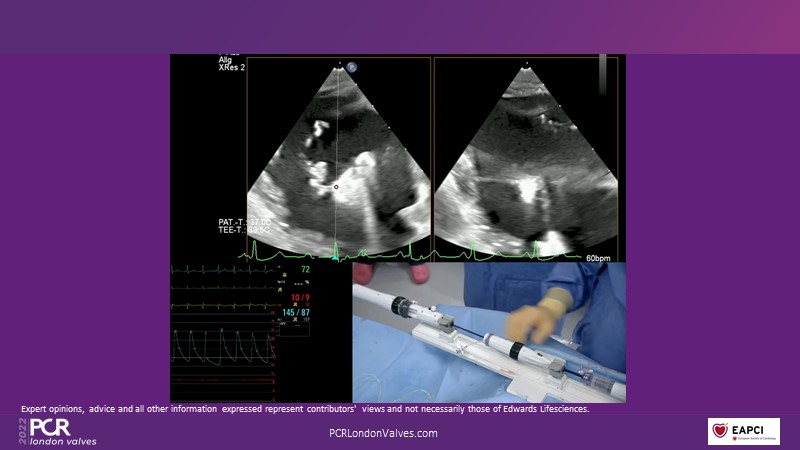

This innovative session takes you through the patient selection and anatomical characteristics when selecting amongst the different transcatheter options to treat tricuspid regurgitation, followed by a recorded demonstration using the PASCAL Precision repair system.

- To participate in a recorded demonstration using the PASCAL Precision repair system for the treatment of tricuspid regurgitation